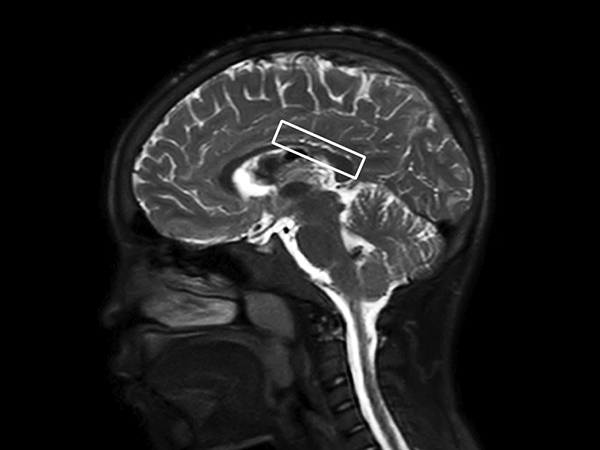

In this case, a 10-year-old girl thrown from a horse. The SWIp images provided increased visibility of the corpus callosum injury compared to the T2-weighted, diffusion weighted and gradient echo images, see the box in the images. SWIp also provides increased visibility of the cortical contusion (arrows) compared to gradient echo imaging. In this case, SWIp helped to characterize the extent of the patient’s injury, which is important to know for short term care and longer term prognosis and rehabilitation.

Sagittal T2w SSh TSE